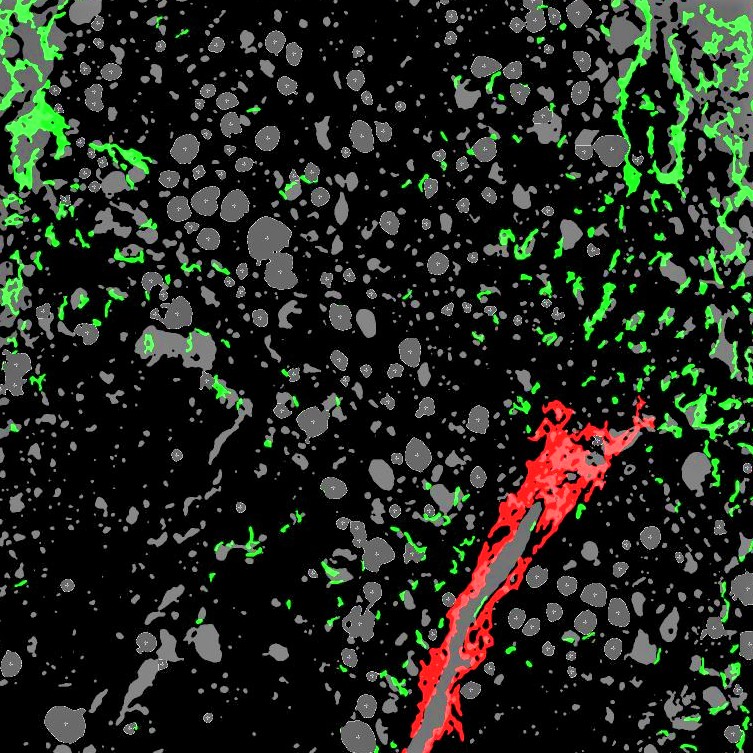

NASH Liver Biopsy Processed by FibroNest

PharmaNest is an image analysis company focused on the development and validation of novel standards for the quantification of Fibrosis for drug discovery and development. Recently, PharmaNest announced the launch of its FibroNest cloud-based and multi-vendor platform for the automated quantification of Fibrosis for non-alcoholic fatty liver disease (NAFLD) and non-alcoholic steatohepatitis (NASH), for research-only-use projects at this time.

As a multi-vendor platform, it is compatible with all kinds of formats of digital images of tissues and biopsies generated by Two-Photon and Second Harmonic microscope or from digital images from conventional pathology stained slides (Picro Sirius Red, Trichrome or Antibody stains for fibrosis), acquired by FDA-approved digital pathology slides scanners.

The Platform has been engineered to quantify the fibrosis phenotype in three phenotypic dimensions, including more than 40 traits and +350 parameters. The model has been validated to establish a continuous score for the assessment of the severity and progression of fibrosis in 20+ pre-clinical models and, most recently, in clinical PBC, Adult NASH and Pediatric NASH, but it remains as an investigational tool at this stage.